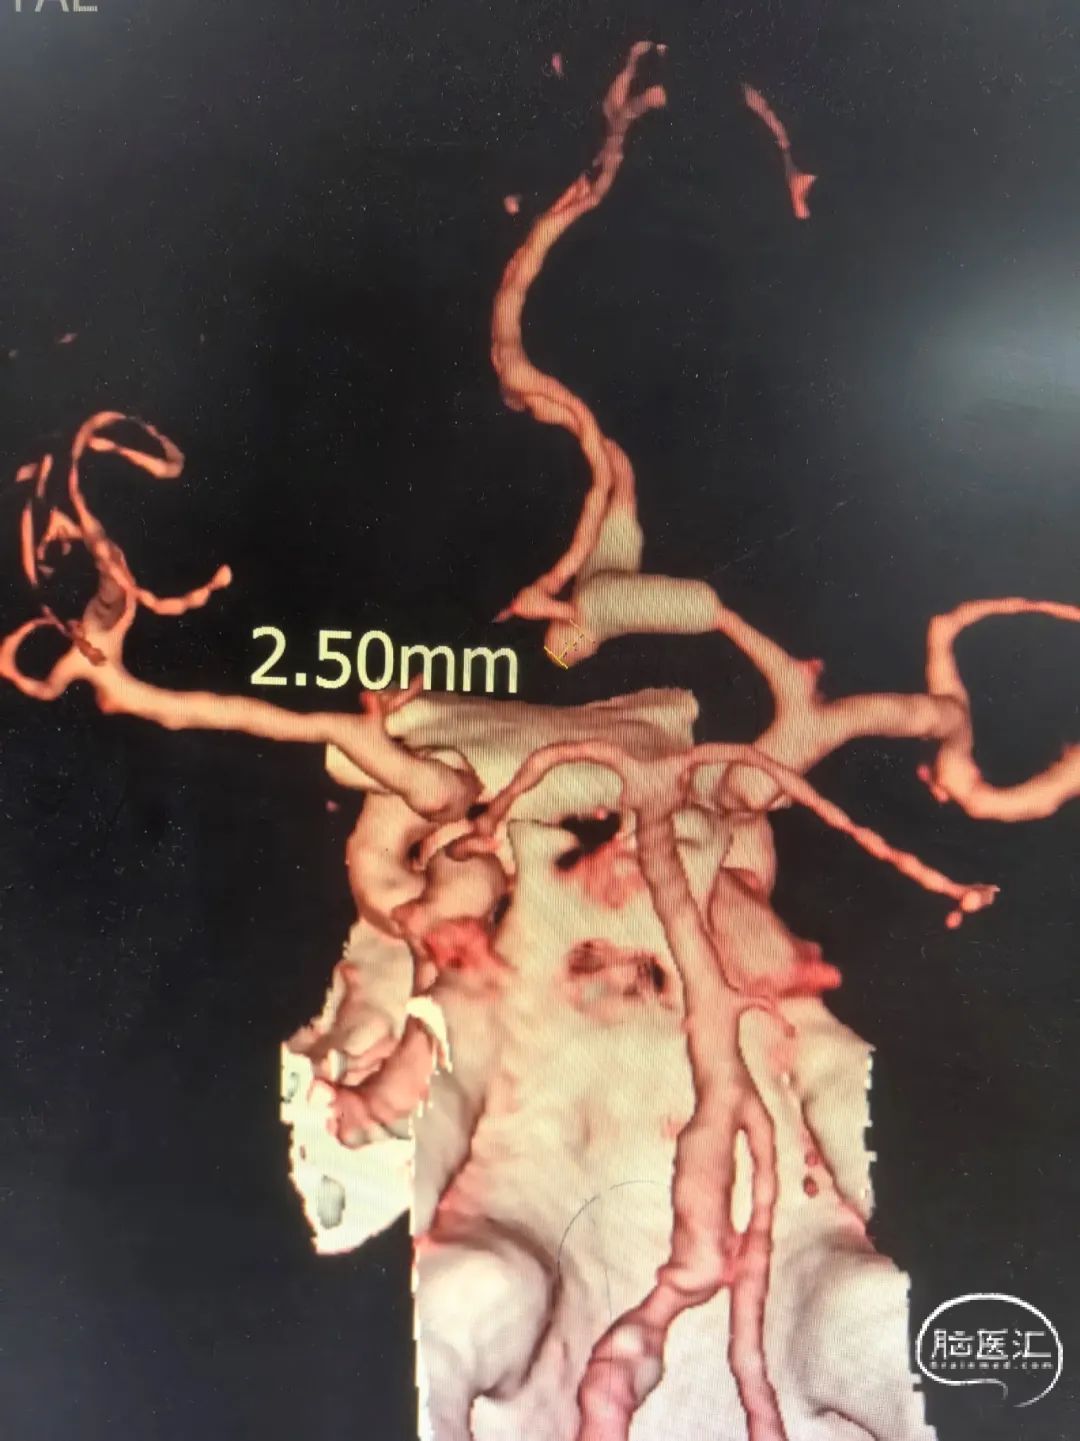

2025-1-19 DSA造影3D重建及方案讨论:

DSA造影3D重建测量

拟行脑动脉瘤密网支架置入术。

2.5mm*15mm Surpass Evolve密网支架,支架锚定区为右侧A2~A1